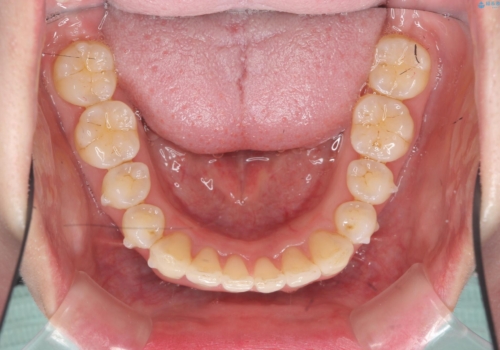

インビザライン で治す 出っ歯の治療

- 前歯の突出感、出っ歯の治療を希望され来院されました。

インビザラインを用いた治療計画を立て、しっかりと出っ歯を治すためにマイクロインプラントを併用します。

マイクロインプラントを併用することでしっかりとマウスピース全体を後方へ引き、前歯の突出感を改善することができました。